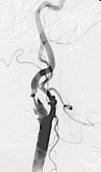

Fig. 3. --(A) Imagen de reconstrucción volumen rendering. (B) Reconstrucción mini-MIP de la arteria carótida izquierda. Estudio de angio-CT donde se observa la bifurcación carotídea y la porción proximal de ACI sin ninguna estenosis de significación.